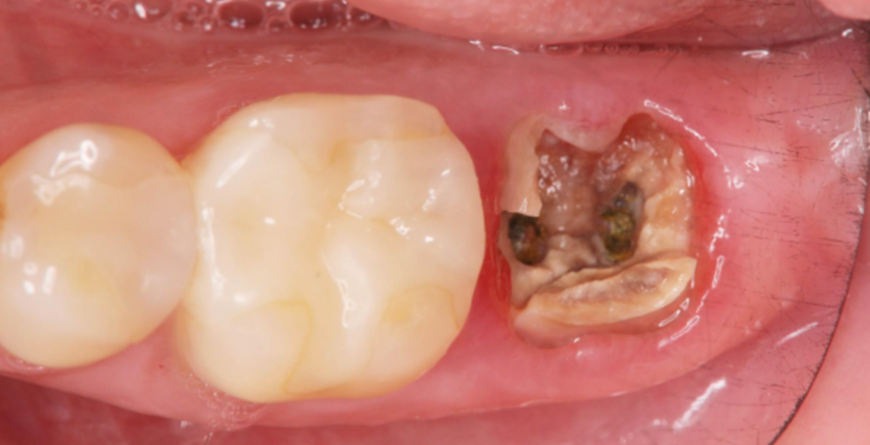

1.After thorough communication with the patient, the residual root of Tooth #47 was extracted.

Pre-extraction images